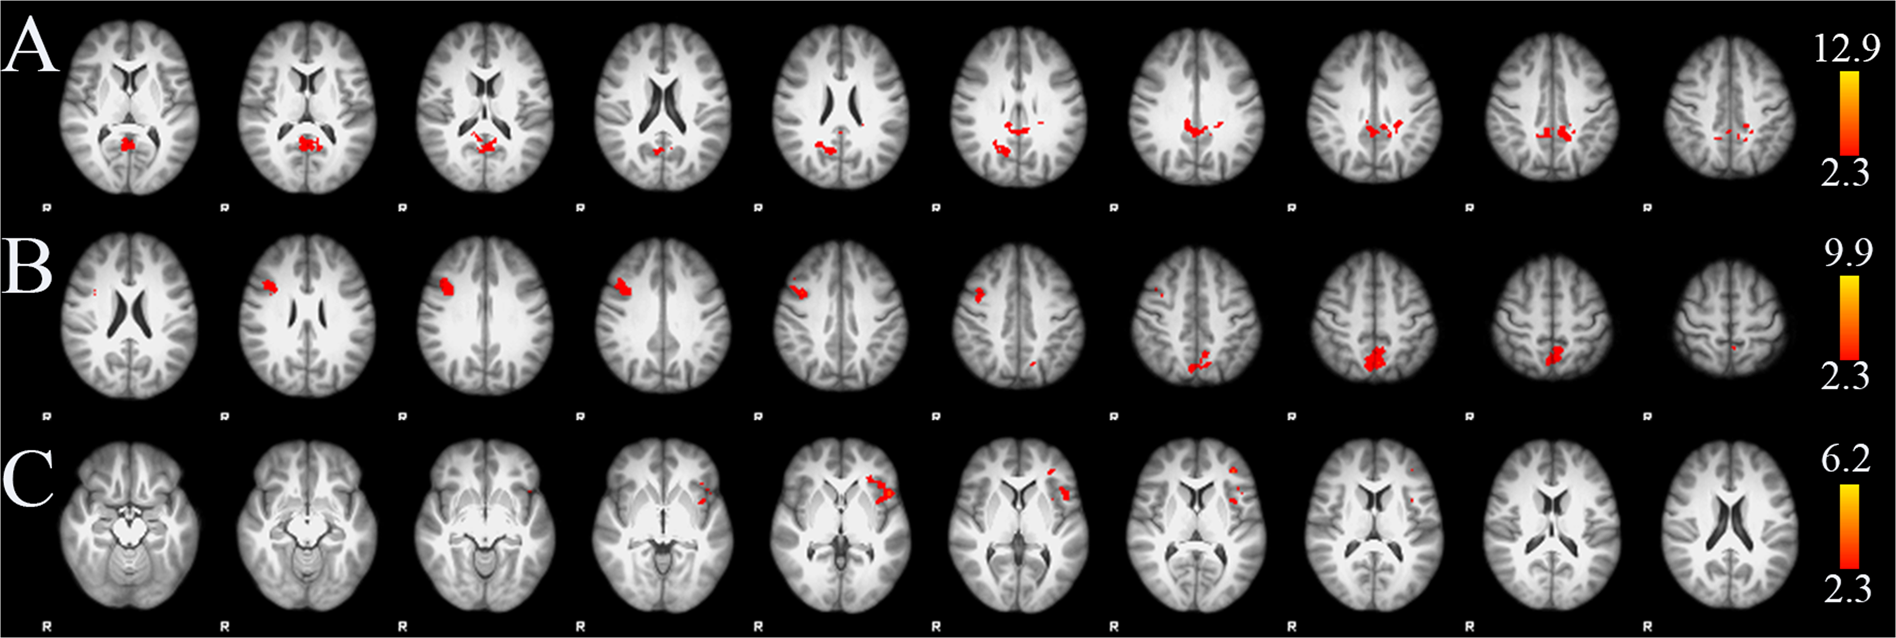

Figure 3

From: Internet addiction and functional brain networks: task-related fMRI study

Group level negative associations between PIUQ and BOLD signal changes during incongruent condition in verbal Stroop task (A) and non-verbal Stroop-like task (B). Group level positive associations between PIUQ and BOLD signal changes during incongruent_minus_congruent contrast in Stroop task (C). Images were thresholded using clusters determined by Z > 2.3 and a corrected cluster significance threshold of p = 0.05. Axial slices are shown in radiological convention for MNI slice coordinates from Z = 8 to 48 mm in (A), Z = 22 to 62 mm in (B) and Z = −16 to 24 mm in (C).